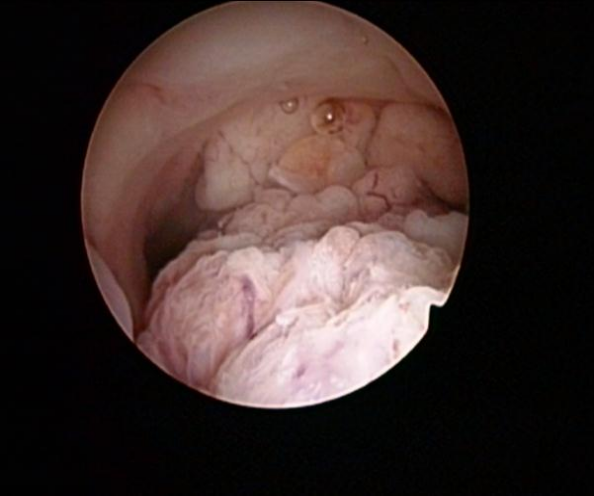

患者于入院前半年因无明显诱因出现阴道流血,遂就诊于我院,行妇科B超提示:子宫内膜占位性病变;行宫腔镜检查提示:宫腔布满结节状病灶,质地糟脆,考虑子宫内膜癌,宫颈未受累;宫腔镜下活检病理提示:低分化子宫内膜样腺癌;现患者为求进一步治疗,就诊于我院,我科以“低分化子宫内膜样腺癌”收住。